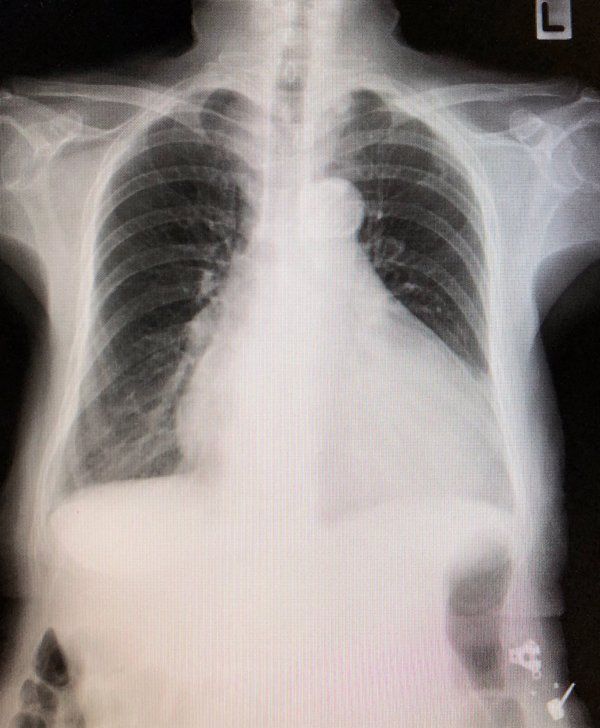

腺樣囊性癌肺部轉移多發(fā)結節(jié)屬于較為嚴重的疾病狀態(tài),需要積極處理。

此病癥主要是由于腺樣囊性癌發(fā)生了肺部轉移,形成了多個結節(jié)病灶,此時病情已處于中晚期階段,如果不及時治療可能會對生命造成威脅。因此,建議盡快進行系統(tǒng)評估以制定最佳治療方案,同時注意身體休息,保持良好的心態(tài),積極配合醫(yī)生的診治工作。

如果患者的身體狀況允許,可以考慮化療、放療或靶向治療等方法來控制腫瘤的發(fā)展。

針對腺樣囊性癌肺部轉移多發(fā)結節(jié)的治療需綜合考慮手術切除、放療和化療等多種手段,并密切監(jiān)測病情變化?;颊邞ㄆ趶筒橛跋駥W檢查以及血液指標,以便及時發(fā)現(xiàn)病情進展并調整治療策略。